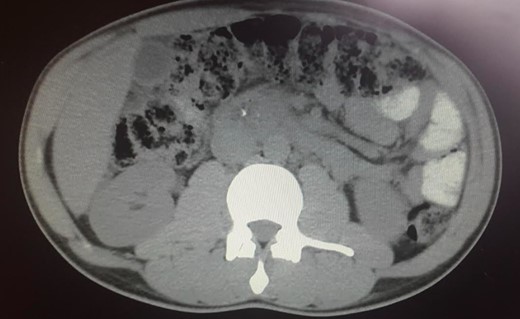

The abdominal exam revealed a soft, non-distended, non-tender abdomen, without any palpable masses, organomegalies or lymphadenopaties. Blood chemistry showed a cholestatic pattern: bilirubin 6.61 mg/dl, alkaline phosphatase 434 U/l, gamma-glutamyl transpeptidase 374 U/l, alanine transaminase 542 U/l and aspartate transaminase 228 U/l. Lipase, amylase and complete blood count showed regular values. Abdominal ultrasound revealed dilatation of the intra and extrahepatic bile ducts and the pancreas was enlarged and hypoechoic, compatible with inflammation. CT scan was performed to discard a neoplastic obstruction and confirmed an intrahepatic biliary ductal dilatation (Fig. 1) and a dilatation of the distal bile duct with no luminal lesions (Fig. 2).

Pancreatic CT scan. General dilatation of the intrahepatic biliary tree and terminal common bile duct.